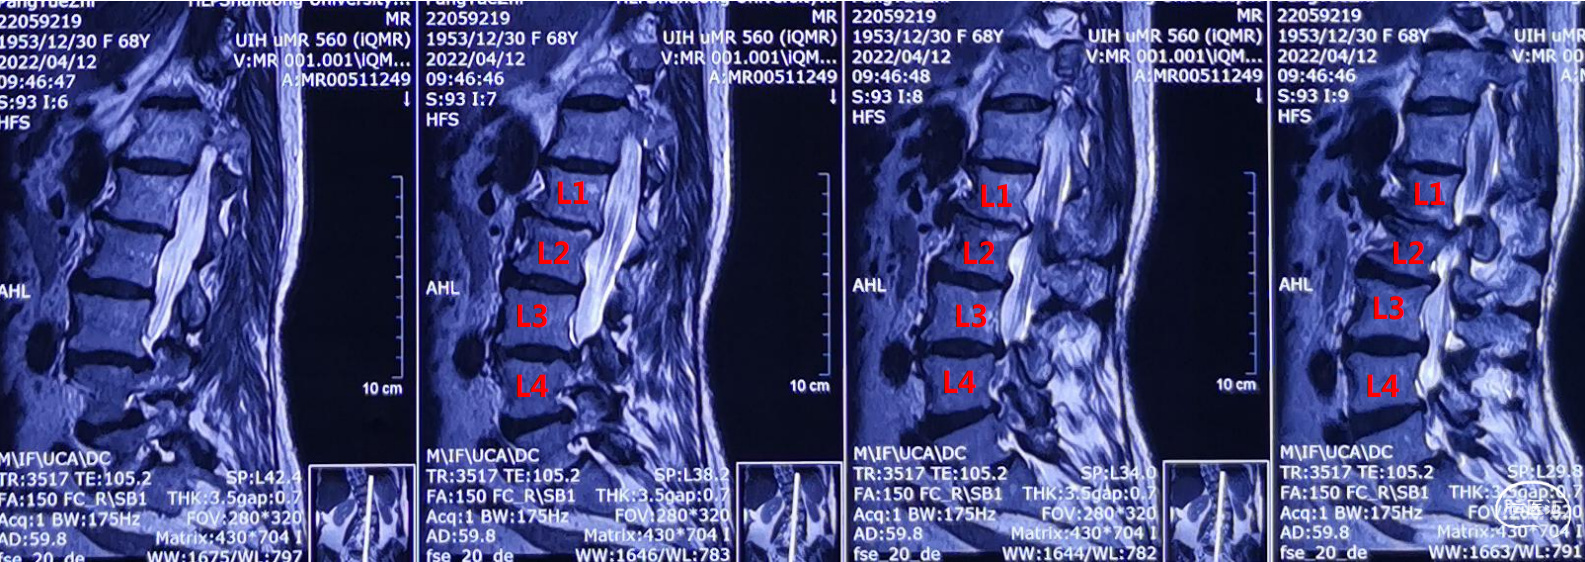

作者:姜政 韩利章 张鑫

患者,庞某某,女,68岁,帕金森氏病DBS术后3年余。

主诉:右侧腰部疼痛5年,加重并伴有左侧下肢疼痛、麻木、无力、跛行3年。 现病史:患者自诉5年前开始出现右侧腰部疼痛,3年前出现腰痛加重伴有左侧下肢疼 痛、麻木、无力,无法长时间行走(跛行50米左右),适当休息后病情可略缓解。